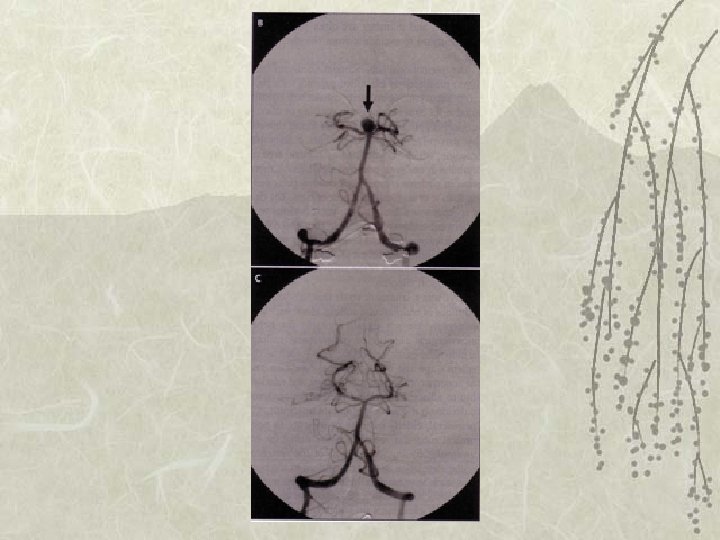

Vasospasme Levée du Vasospasme après ttt endovasculaire

Traitements du Vasospasme (4) v Angiographie cérébrale – Traitement PRECOCE: • nimodipine in situ, corotrope, • angioplastie, • évolution, situation. v Avenir… – Anti-endothéline. Etude CONSCIOUS